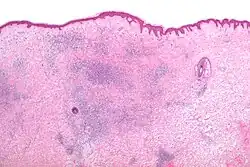

Microscopic appearance

Skin biopsies are not indicated for bites or stings, since the histomorphologic appearance is non-specific. Bites and stings as well as other conditions (e.g. drug reactions, urticarial reactions, and early bullous pemphigoid) can cause microscopic changes such as a wedge-shaped superficial dermal perivascular infiltrate consisting of abundant lymphocytes and scattered eosinophils, as shown in the adjacent figure:[12]